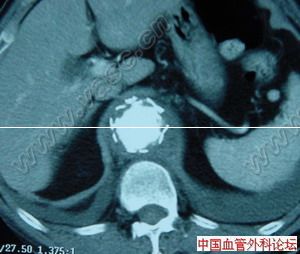

主動脈竇動脈瘤破裂主動脈竇動脈瘤是一種罕見的先天畸形,約占先天性心臟病患病率的2%~3.56%,其破入右室者最多,其次為右房。發生原因主要是胚胎期竇壁中層彈力纖維發育不良,在主動脈內高壓影響下,該薄弱處逐漸變薄擴張,呈囊袋狀突出,當壓力突然增加時破裂,由於主動脈和破入心腔間存在著較大的壓力階差,可產生大量的左向右分流,因而導致全心容量負荷增加,特別是外破口較大或破入右房者,病情進展快,容易發生充血性心力衰竭,部分患者易繼發心內膜炎、心律紊亂、腎功能衰竭等嚴重併發症。臨床多表現為起病急、進展快。一般認為,主動脈竇動脈瘤破裂之前多無明顯症狀和體徵,一旦破裂,即產生劇烈胸痛及顯著的血流動力學改變。破入右室、右房者可出現右心衰竭,呈進行性加重。體徵有胸骨左緣第3、4肋間連續性響亮機器樣雜音,常伴有肺動脈高壓、右心功能不全及脈壓差增大的表現。首次聽診往往有主動脈瓣受損的印象,易誤診為主動脈瓣關閉不全,本例即是此種情況。超聲心動圖是最佳的無創診斷法,可直接顯示主動脈竇動脈瘤的起源形態、突入的心腔位置、竇瘤破口大小、是否合併其他心臟畸形、分流的性質、時相、最大流速,提供血流動力學資料。一旦瘤體破裂,預後不良,可在數周至數月內因嚴重併發症死亡。內科治療只能起到短暫的減輕作用,手術治療往往可以獲得滿意的效果。該戰士因沒有及時手術,導致急性腎功能衰竭並時間過長,多臟器衰竭而死亡。